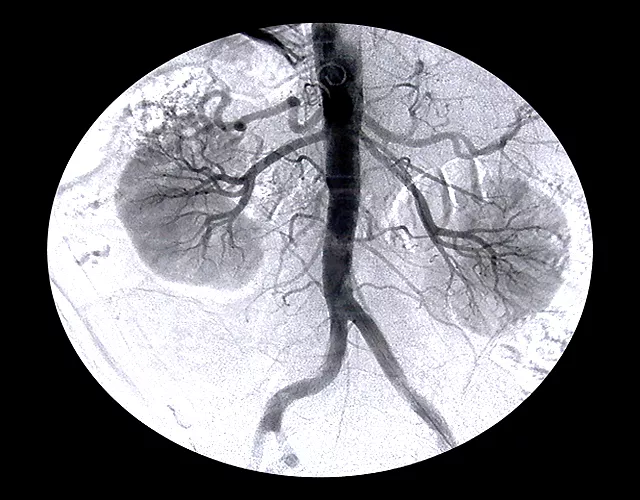

“Kidneys are an important organ of the body which excretes unwanted material out of the body while also maintaining a balance between water, salt and acidity in the body. The kidneys also control blood pressure and play an important role in the production of vitamin D and blood,” Dr Sultan said, adding that around 20,000 people die of kidney failure every year.